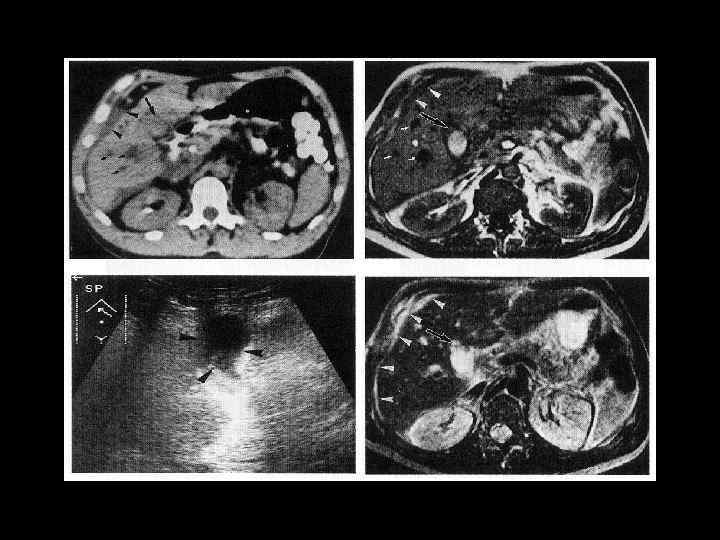

АКТУАЛЬНЫЕ ВОПРОСЫ РЕНТГЕНОЛОГИИ ЛУЧЕВАЯ ДИАГНОСТИКА ЗАБОЛЕВАНИЙ ЖЕЛЧЕВЫДЕЛИТЕЛЬНОЙ СИСТЕМЫ Желчекаменная болезнь КТ семиотика

АКТУАЛЬНЫЕ ВОПРОСЫ РЕНТГЕНОЛОГИИ ЛУЧЕВАЯ ДИАГНОСТИКА ЗАБОЛЕВАНИЙ ЖЕЛЧЕВЫДЕЛИТЕЛЬНОЙ СИСТЕМЫ Желчекаменная болезнь МР семиотика